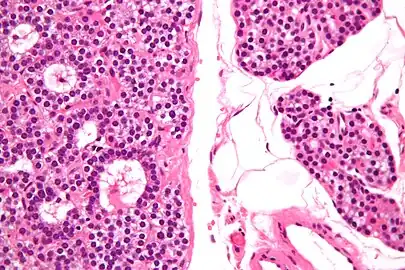

- Micrograph of a parathyroid adenoma (left) and normal parathyroid gland (right). H&E stain.

- Normal parathyroid gland with prominent adipose tissue is seen on the right of the image.-High magnification

- Histopatholgical image of parathyroid adenoma in a patient with primary hyperparathyroidism. Hematoxylin and eosin stain. Another view of the same lesion